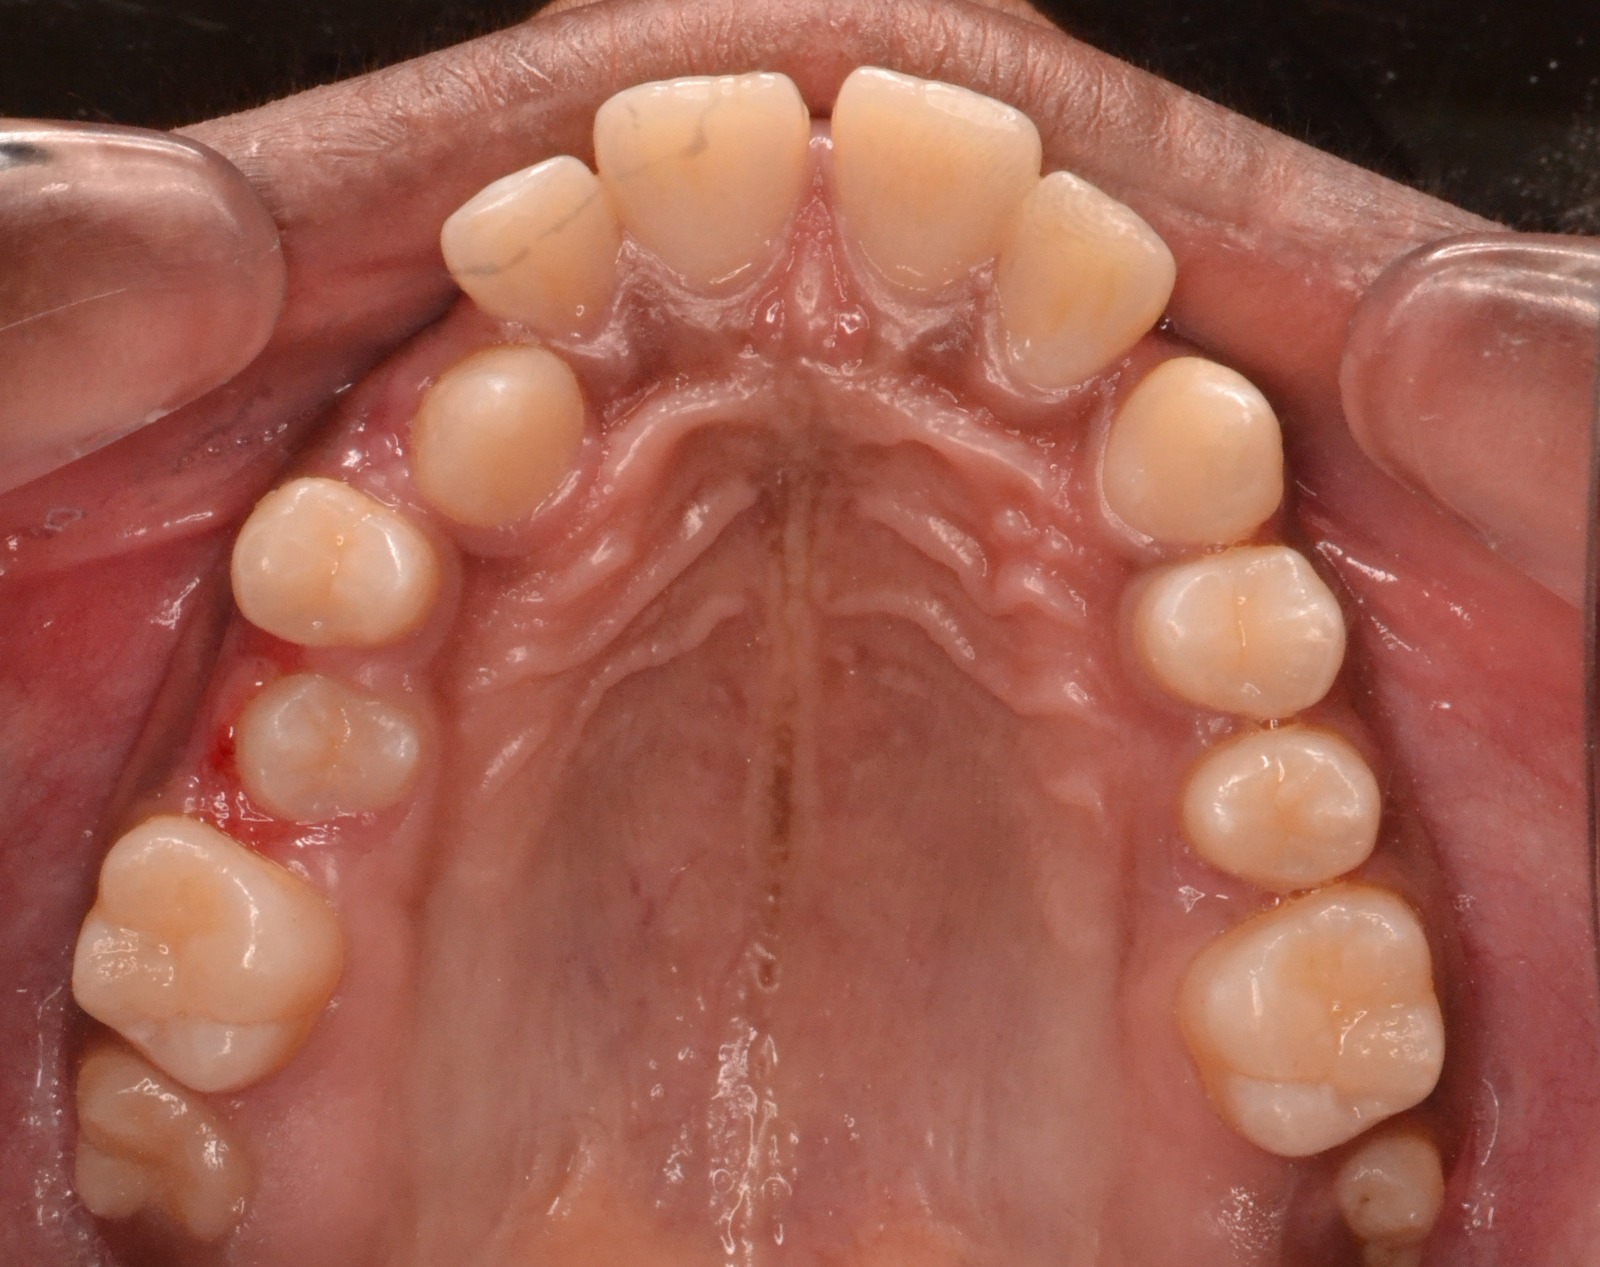

Sairam dental care located in Dharmapuri, with Leading Dentist In Oddapatti, is the Dental Hospital with exclusive root canal, Braces & Invisalign center. Led by renowned Drs Raghuraaman ( Periodontist) and Nivetha Raghuraaman ( Orthodontist) Sairam dental care offers gum treatment with expertise in laser, root canal treatment and digital smile correction with advanced technology aim to focus on aesthetics, comfort and precision. The clinic also specializes in Invisalign treatment, digital smile makeover, laser gum care, dental implants, root canal therapy, extractions and full-mouth rehabilitation blending compassionate care and clinical excellence.

Our professional, experienced, and passionate dentists make us the best choice for Invisalign treatment in Dharmapuri, providing top-notch dental services.